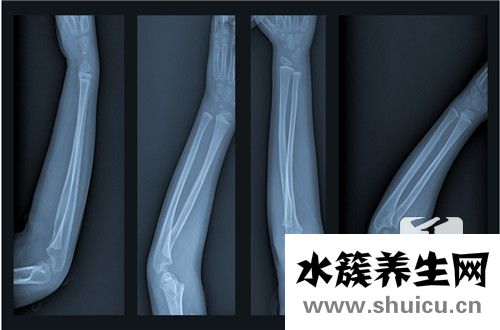

女性骨質疏松是缺鈣的疾病,長期缺乏體育鍛煉的女性也會引起骨質疏松。所以女性有骨質疏松,就要多攝入鈣和鋅,提高運動強度。藥物可以選擇服用甲狀旁腺激素或二磷酸,但應配合醫生立即治療。在骨質疏松...